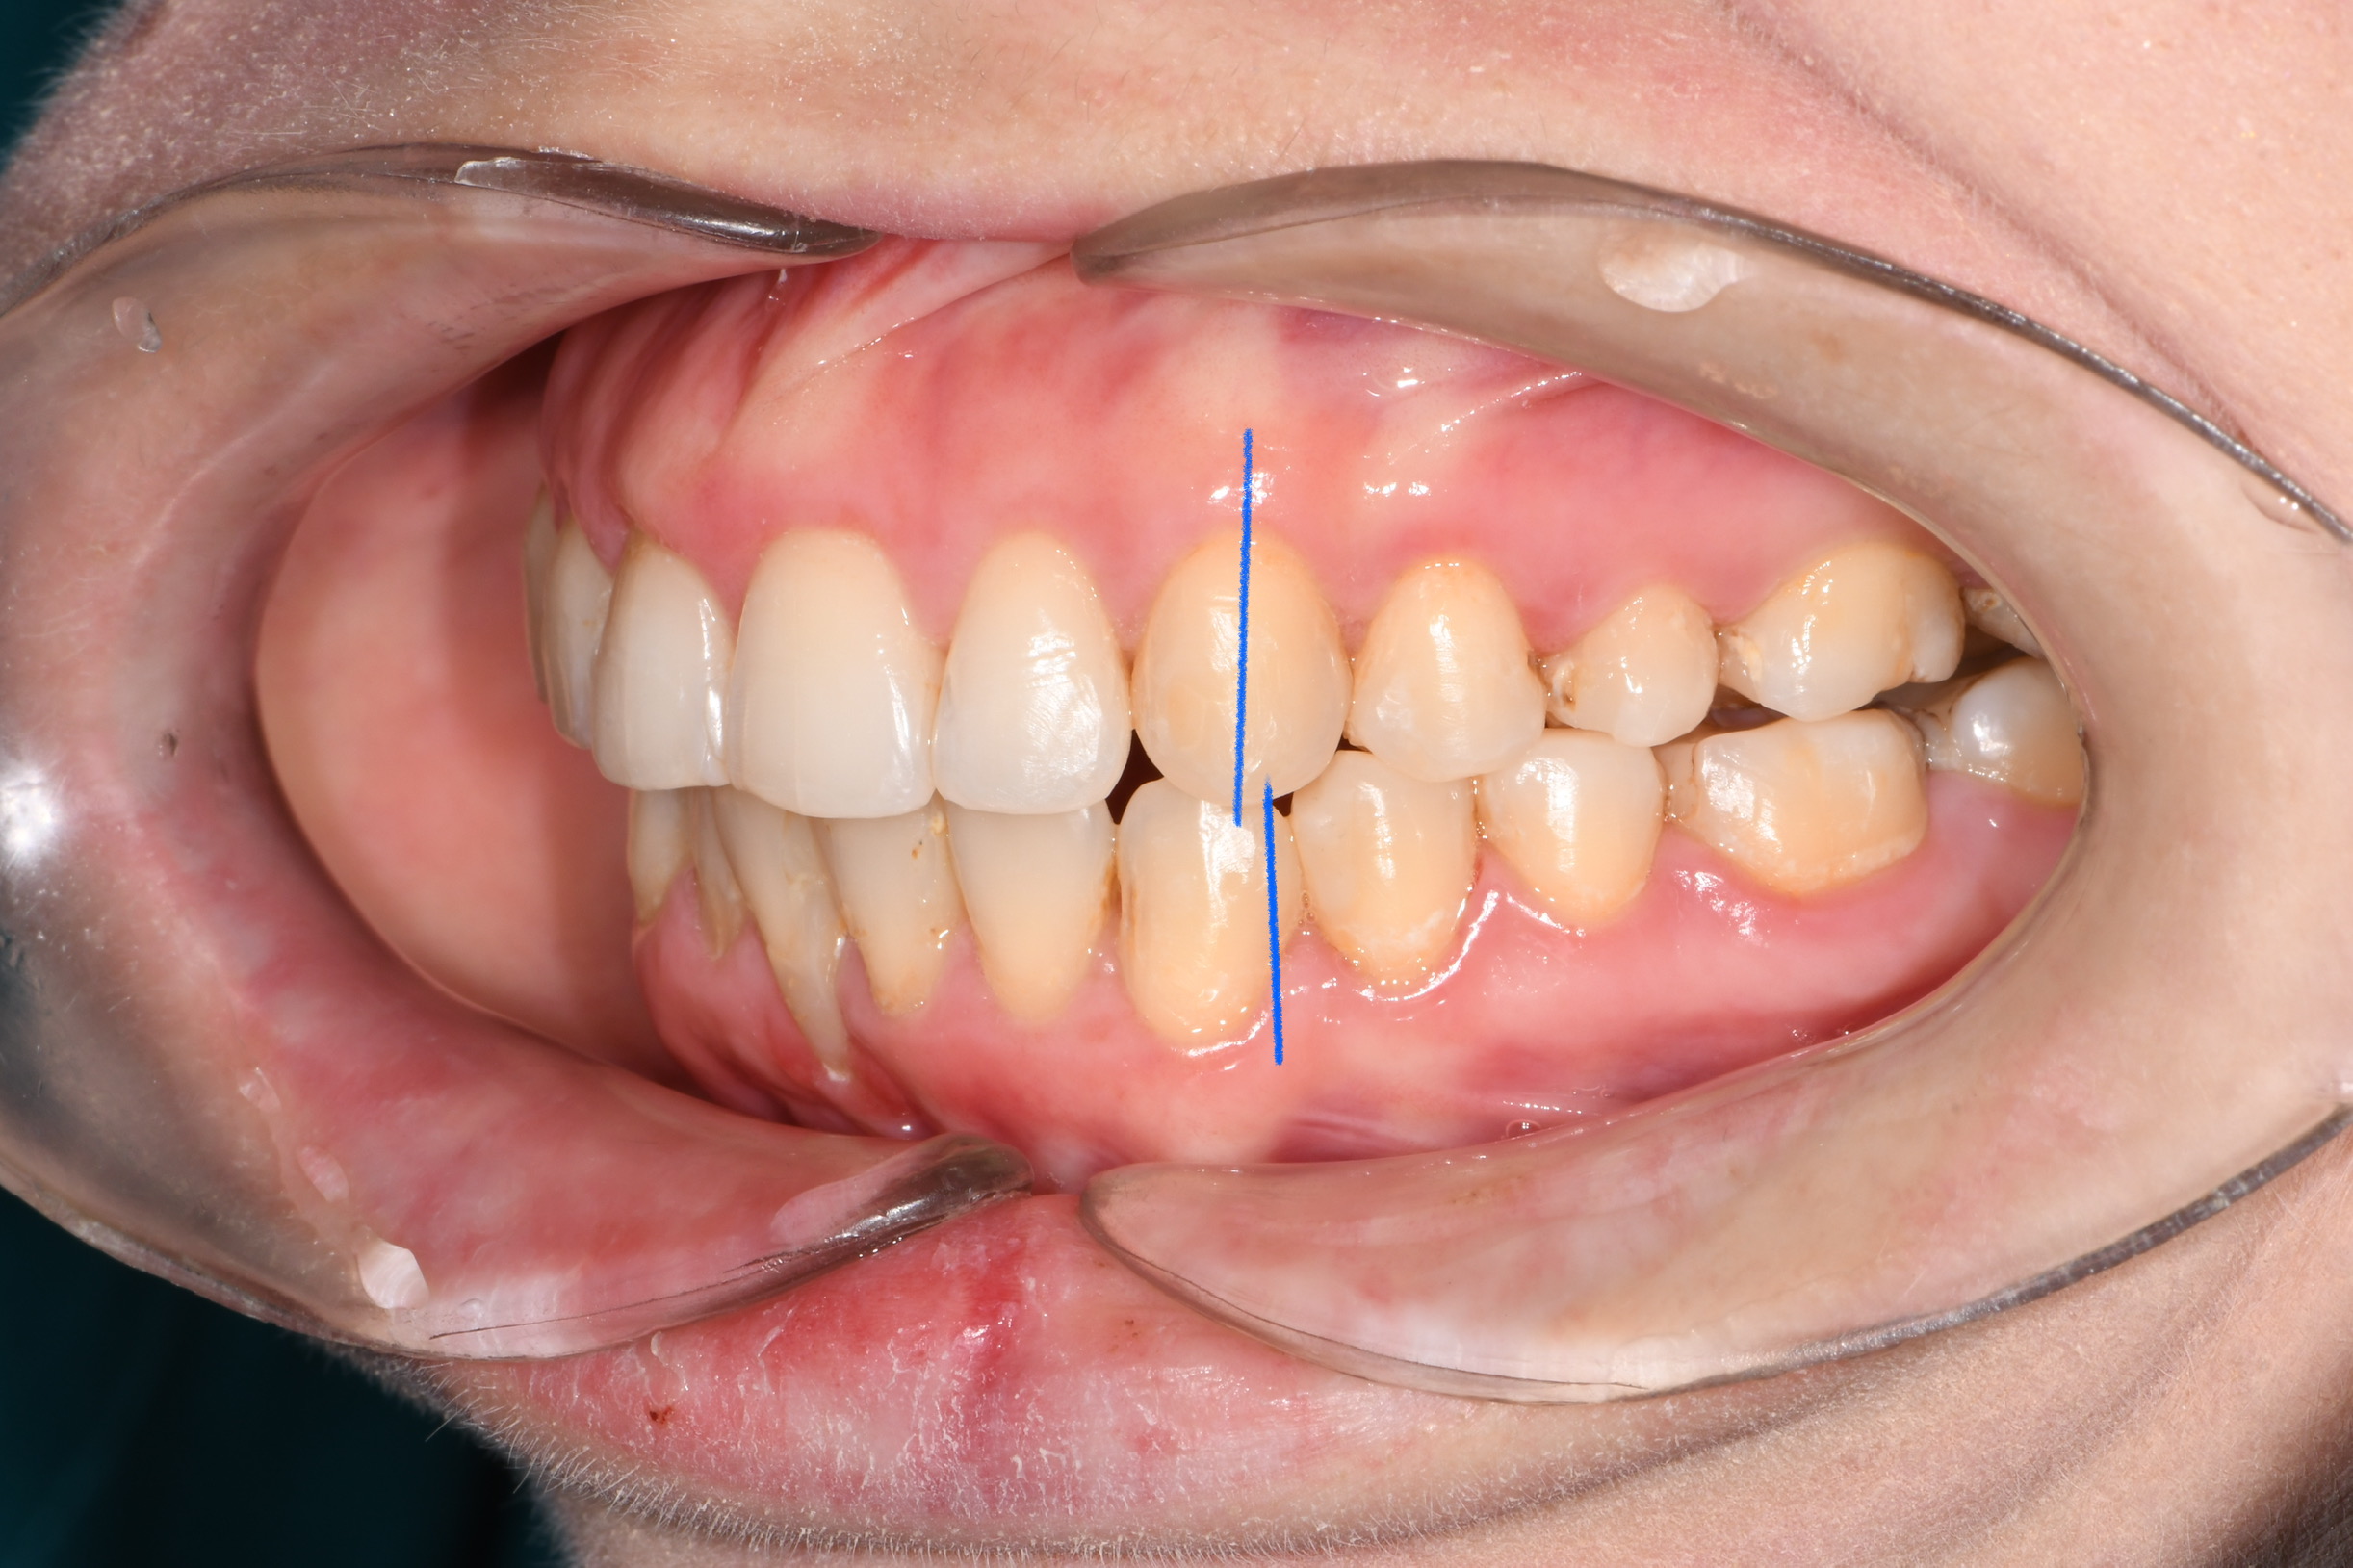

Az elmúlt évekből rengeteg szakmai referenciát tudnánk bemutatni, amelyek különböző fogszabályozási problémákat oldottak meg. Válogatva a több száz esetből, ezen az oldalon olyan képeket, információkat igyekeztünk bemutatni, amelyeknek a segítségével a jövőbeni pácienseinknek azt tudjuk üzenni: A Te fogsorod is lehet gyönyörű!